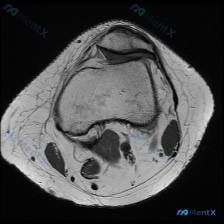

今天碰到一个很典型的「临床-影像矛盾」病例,整理出来和大家一起讨论一下。 病例核心信息 问题:临床高度怀疑膝关节软骨异常,仅提供1张膝关节MRI-T1序列轴位影像(髌股关节层面),要求读片分析。 影像读片结果: 1. 骨性结构:股骨远端、髌骨骨皮质连续,软骨下骨光滑,骨髓脂肪信号均匀,未见异常信号灶...

今天遇到一个有意思的读片问题:只给了一张膝关节轴位MRI,问这里有没有软骨异常,整理一下分析思路分享给大家。 基本病例/影像信息 提供的是膝关节单张轴位MRI扫描图像,可识别的解剖结构包括:前方的髌骨、中部的股骨内外侧髁与髁间窝、髌股关节间隙,以及周围部分软组织。 客观影像所见 1. 软骨结构:髌骨...

看到一份针对单张膝关节MRI的软骨异常评估咨询,整理了完整的分析思路分享给大家。 病例/影像基础信息 问题核心:用户提供单张膝关节轴位T1加权MRI图像,询问图像中是否存在软骨异常。 影像所见(基于提供图像): 1. 扫描层面为膝关节轴位,涵盖股骨远端滑车区与髌骨 2. 股骨髁、髌骨骨髓信号正常(T...

刚遇到一份有意思的膝关节影像病例,整理出来和大家分享一下思路。 病例基本信息 这是一份膝关节MRI T1序列轴位单张图像,核心疑问是评估是否存在「软骨异常」。 影像读片结果 1. 扫描层面是膝关节上部,主要显示髌股关节(髌骨+股骨滑车)和股骨髁 2. 髌骨软骨下骨、股骨髁骨皮质轮廓清晰,骨松质信号均...

病例读片:膝关节软骨异常的影像陷阱 先给大家看一下这份病例的基本影像资料:这是一张膝关节MRI-T1加权序列的轴位图像,扫描层面位于股骨远端髁间窝与髌股关节层面。 影像基本信息整理 1. 骨骼结构:股骨远端骨皮质、骨髓信号正常,髌骨形态完整,骨皮质连续,骨髓信号无异常; 2. 关节软骨:髌骨后方关节...